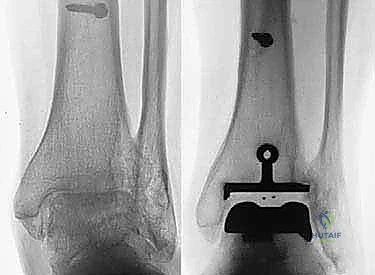

- الأشعة السينية (X-rays) بوضعية الوقوف: وهي الأداة الذهبية للتشخيص. صور الأشعة والوزن محمل على القدم (Weight-bearing X-rays) تظهر بدقة مدى تآكل الغضروف (ضيق المسافة المفصلية)، وجود نتوءات عظمية (Osteophytes)، وأي انحراف في المحور الميكانيكي للساق.